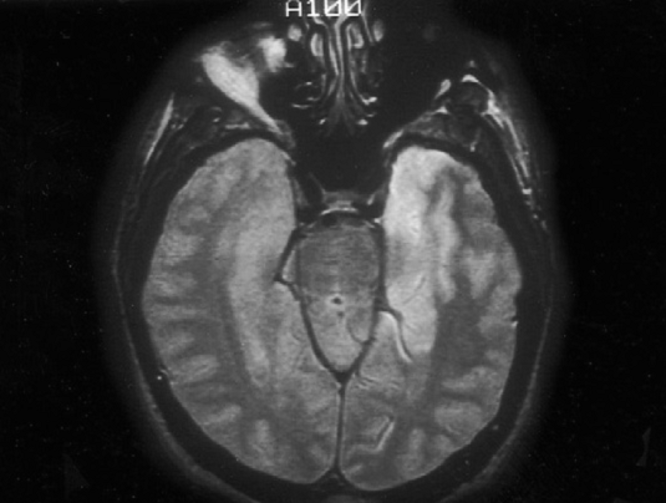

RMN: Edema temporal o frontal, involucro bilateral temporal casi patognomónico